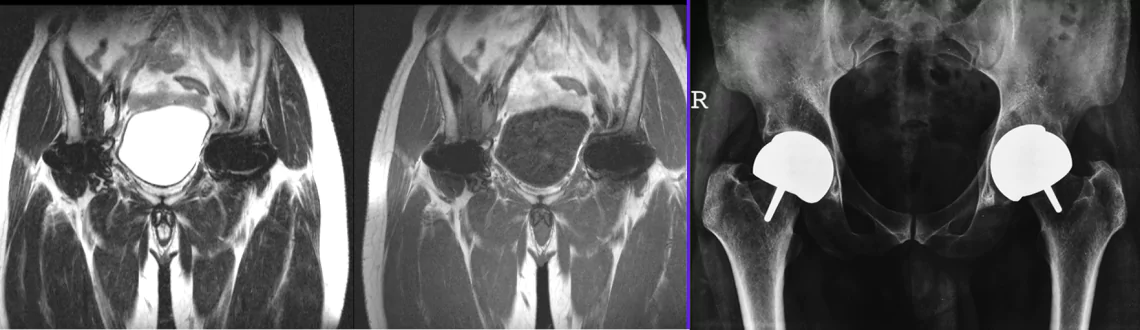

At Picture This, we’re proud to offer Mumbai’s most advanced MARS (Metal Artifact Reduction Sequence) MRI, using the powerful Philips 3.0T Ingenia CX system. MARS MRI is specifically designed to produce crisp, diagnostic-quality images in areas with metal implants-overcoming the limitations of conventional MRI.

MARS (Metal Artifact Reduction Sequence) MRI uses specialized pulse sequences and software algorithms to significantly reduce distortion, streaking, and signal voids caused by metal prostheses, orthopaedic hardware, or dental implants. This enables clear visualization of surrounding soft tissues, joints, and organs for accurate diagnosis and planning.

1. Post‑operative Orthopaedic Evaluation - hips, knees, spine, shoulder implants

2. Implant Surveillance - evaluation around joint replacements, plates, screws